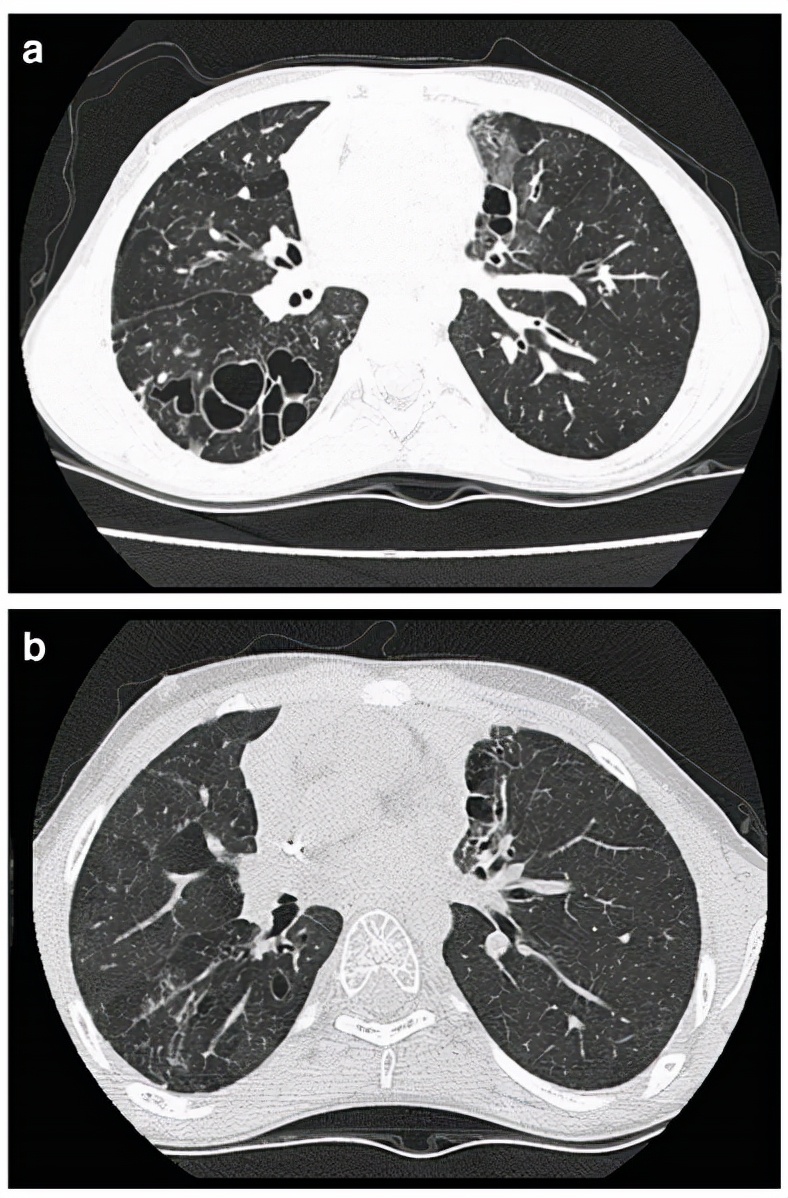

6、哪些免疫功能低下的CAP患者中,最初的经验性治疗应覆盖 曲霉菌?

图:肿瘤患者接受化疗存在严重和长期的中性粒细胞减少,且影像学上表现为结节周围存在环状磨玻璃影(晕轮征)和/或空洞。

图:肿瘤患者接受化疗存在严重长期的中性粒细胞减少且影像学上表现为结节、反晕征或胸腔积液。